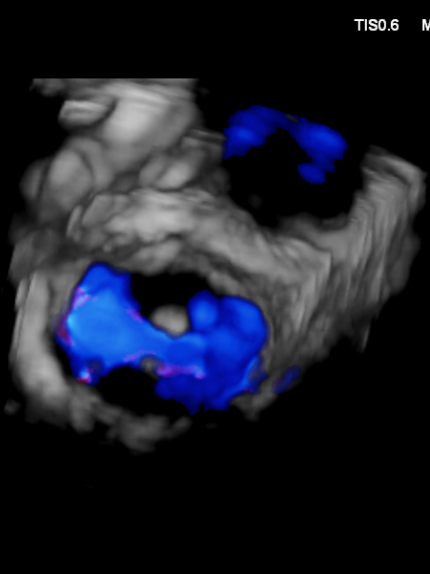

3D MV View: 二尖瓣前后瓣叶对合不全,A2/P2稍偏1区可见未闭间隙。PISIA主要来源于A2/P2区域。

2.X-plane切面调整瓣膜夹的位置:主要定位PISIA最明显的A2/P2区,分别二尖瓣交界联合切面和 LVOT切面调整夹子轴向,同时在3D切面上观察夹子方位和区域,瓣膜夹位置良好,轴向和方位均理想后,捕获A2/P2偏1区处的前后瓣叶,逐渐关闭瓣膜夹,TEE显示二尖瓣反流明显减轻至微量,3D视角显示组织桥连续完整,瓣叶抓捕稳定。彩色血流提示微量的瓣膜反流,测量平均跨瓣压差3mmHg,复查左上肺静脉血流频谱恢复正向,手术效果理想,逐步释放瓣膜夹系统撤出体外。